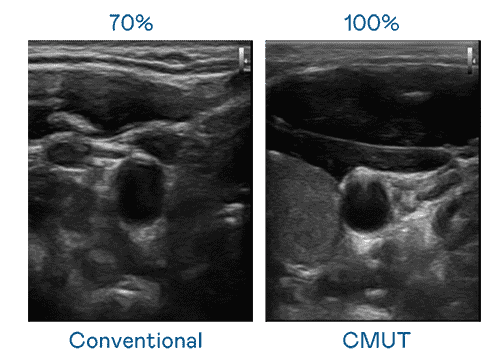

CMUT 技术是一种用电容式微机电元件来产生超音波讯号的技术。。。。与传统 PZT 压电式技术相比,,CMUT 频宽增加 30%,,,,更宽频的超音波讯号让影像解析度大幅提升,,,是实现高影像品质医疗超音波扫描、、促进精准医疗发展的关键技术。。。

大频宽带来超清晰影像

超音波影像的解析度高低,,,,首先取决于探头能发出的讯号频宽。。尊龙集团 CMUT 可提供高清晰的超音波讯号,,提供高频宽、、高灵敏度、、、、影像纹理细节更高的超音波影像,,协助医护人员缩短影像判读时间及利用精准的医疗影像进行诊断。。。。